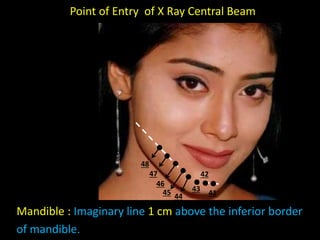

1. The document discusses various intra-oral radiographic techniques including the paralleling cone technique and bisecting angle technique.